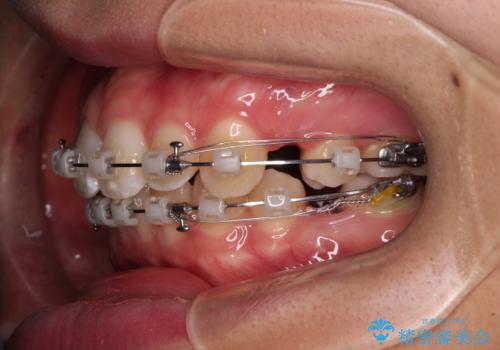

- 矯正装置

- クリアブラケット

- 治療期間

- 2年11ヶ月

- 治療回数

- 30回以上